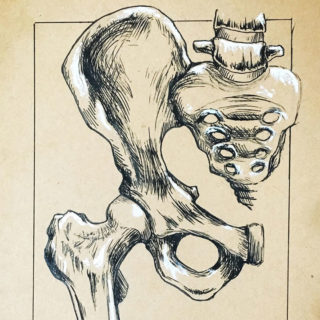

Nádorová onemocnění v oblasti pánve mnohdy vyžadují radiační terapii. Ta však vede k poškození sliznic, které může být spojené s chronickými záněty, jak to vidíme

Avaskulární nekróza hlavice stehenní kosti je závažný stav spojený s odúmrtím kostí, tj. dojde k rozpadu hlavice a narušení kyčelního kloubu. Stav je způsoben narušením nitrokostní krevní